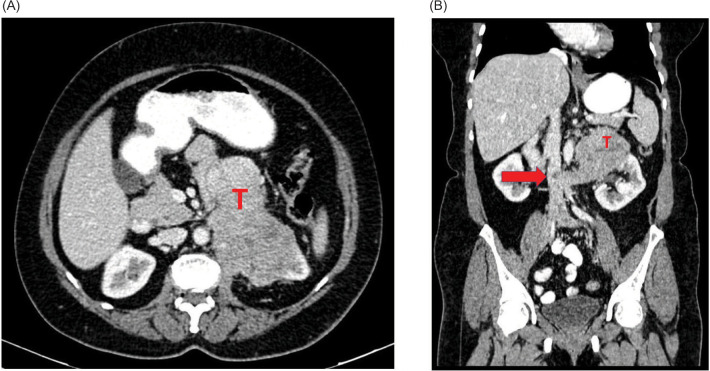

Glomus tumor, arising from glomus bodies (specialized neurovascular structures involved in thermoregulation), commonly occurs in extremities and rarely in viscera. The spectrum of glomus tumors range from benign tumors to tumors with uncertain malignant potential to tumors of the malignant subtype. A vast majority of visceral glomus tumors are benign. Most common visceral tumors arise in the gastrointestinal tract. Glomus tumors of the kidney are a rare entity of which malignant glomus tumors are exceedingly rare. The index patients in the existing case reports were middle-aged males. We report our experience with malignant glomus tumor of the left kidney in a 60-year-old female, with computed tomography (CT) showing involvement of renal vein and inferior vena cava (IVC). Percutaneous biopsy was performed as imaging did not conform to the appearance of a conventional renal tumor and was reported as malignant glomus tumor after immunohistochemistry. After informed decision, the patient and family elected to proceed with surgery. However, intraoperatively, the left renal mass was found to infiltrate the pancreas, duodenum, aorta, and root of the colonic mesentery due to which surgery was aborted. Biopsy obtained intraoperatively again confirmed diagnosis of left renal malignant glomus tumor. She had an uneventful postoperative recovery. Options of treatment were reviewed by a multidisciplinary board. In light of no proven benefit for systemic therapy, she was referred for supportive care. She was under follow-up and she expired after 7 months due to progressive disease. Our literature review focuses on the clinicopathologic features and the current standard of management of malignant renal glomus tumors.